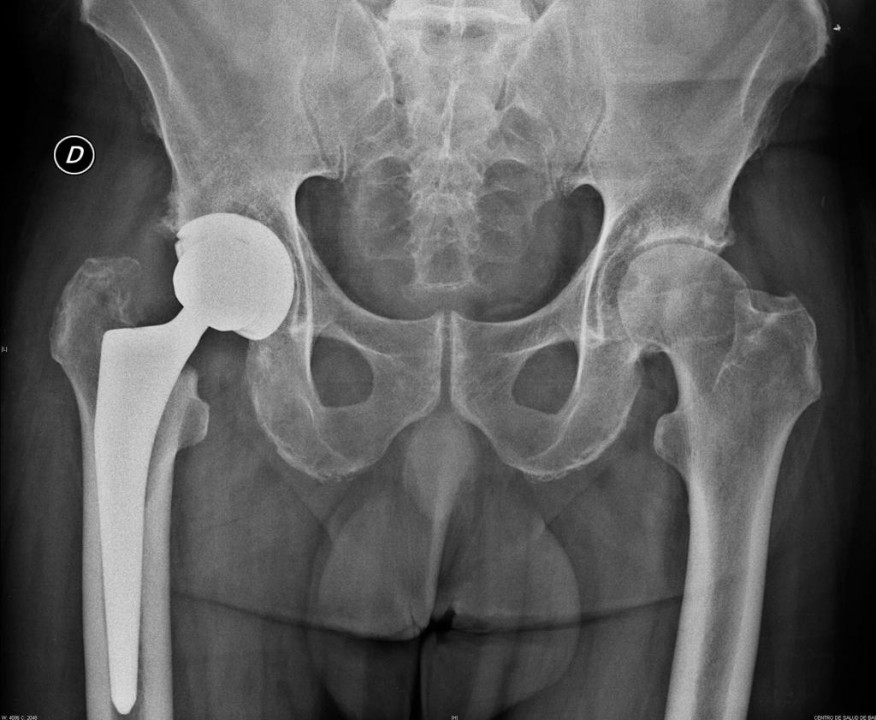

A continuación os mostramos el antes y el después de un caso clínico tratado por nuestro equipo de traumátologos.

Existe una amplia gama de implantes de prótesis de cadera; la elección de cuál es el más indicado depende de diferentes factores y, por tanto, la decisión de toma de forma particular para cada caso.